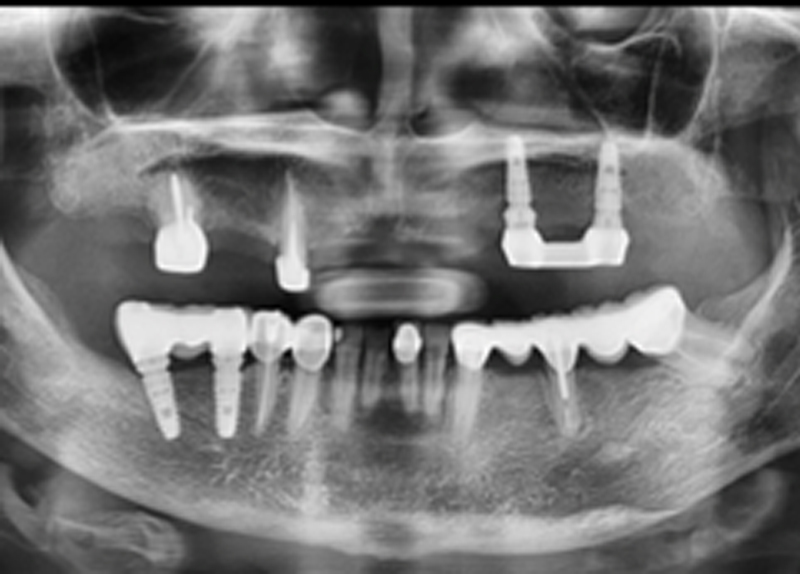

住在澎湖的蘇太太,因為牙齒鬆動,不方便就醫

長期缺牙後 產生咬合面歪斜 下巴偏斜 咀嚼困難

劉南佑醫師以經濟實惠的方式來進行全口重建

★搭配電腦斷層 測量骨頭密度

精準植牙導航 植入植體